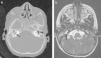

A los 7 meses, consulta por febrícula, fontanela abombada, vómitos e irritabilidad, por lo que se realiza una punción lumbar que muestra una citoquímica similar al episodio anterior y aislamiento de escasas colonias de S. aureus sensible a cloxacilina. Esta vez se observa estado de portador de S. aureus en la madre. Ante una segunda meningitis por el mismo germen, y sospechando un defecto anatómico, se repite la RM, donde se observa una imagen en la fosa posterior compatible con un seno dérmico complicado con un pequeño empiema subdural, además de una hidrocefalia arreabsortiva secundaria a la inflamación (fig. 3 a). En ese momento, se coloca un drenaje ventricular externo, se drenan los abscesos subdurales y cerebelosos, y se extirpa el seno dérmico. A pesar de ello, la paciente presenta deterioro clínico y se realiza nueva prueba de imagen, objetivando abscesos a nivel occipital y de cerebelo (fig. 3b) que obligan a su drenaje. Durante la cirugía, se identifica un quiste dermoide, realizándose exéresis completa del mismo. Se aísla nuevamente S. aureus y se completan 7 semanas de tratamiento con cloxacilina. Como terapia de la hidrocefalia, se coloca una derivación ventrículo-peritoneal. Hasta la fecha (11 meses de edad), no ha presentado nuevas infecciones

a) RM con imagen de difusión en plano axial que muestra seno dérmico infectado en fosa posterior (flecha blanca) con restricción. b) RM sagital T1 poscontraste, donde se muestra el trayecto del seno dérmico subcutáneo (flecha negra), complicado con pequeño empiema subdural en la fosa posterior (asterisco). c) Imagen coronal T2 que muestra hidrocefalia arreabsortiva secundaria a la leptomeningitis y 2 imágenes compatibles con abscesos cerebelosos, asociados con edema. d) Imagen sagital T1 poscontraste con presencia de hidrocefalia y realce en anillo de las imágenes de abscesos intraparenquimatosos cerebelosos (flecha negra).